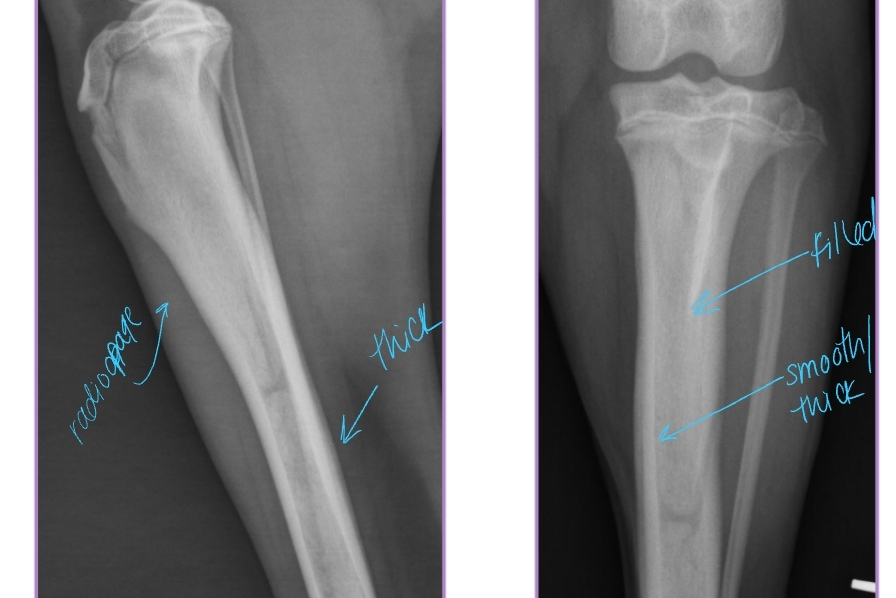

Hypertrophic Osteodystrophy (HOD)

AKA: Scurvy, Moeller-Barlow disease, Metaphyseal osteopathy, Osteodystrophy type I & II, Hypovitaminosis C

Et: Disease of long bones, especially distal metaphyses

Capillary loops become necrotic, vascular congestion, edema, metaplastic cartilage/bone

Forelimbs > hindlimbs

Sig: Juvenile large breed dogs, Rapid growth, <12 months

Cs: Acute onset of lameness, Fever, Lethargy, Anorexia, Diarrhea, Pain at metaphyses, Heat at metaphysis on all 4 limbs!!

Dt: Radiographs

Irregular, radiolucent line in metaphysis adjacent/parallel to physis (“double physeal line”)

Metaphyseal flaring + sclerosis

Subperiosteal and extraperiosteal new bone formation

Tx: Analgesics, antibiotics,self-limiting